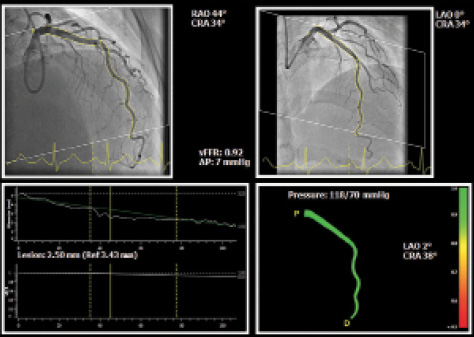

CAAS Workstation QCA-3D. The CAAS Workstation QCA-3D software evolved by applying simplified methods for computation of 3D-QCA–based vessel FFR (vFFR; Figure 1) within CAAS Workstation 8.0. Based on well-validated 3D coronary reconstructions,26,29 the pressure drop is calculated instantaneously by applying physical laws as described by Gould et al.27 Within these physical laws, patient-specific aortic rest pressure is incorporated, as measured during the catheterization procedure. The FAST study, which was a single-center observational study, aimed to validate the software to calculate vFFR offline to assess the correlation as compared with pressure wire–based FFR and study interobserver variability. The study demonstrated a high diagnostic accuracy of vFFR in identifying significant pressure wire–based FFR (area under the curve, 0.93; 95% confidence interval, 0.88–0.97) with low interobserver variability (R = 0.95; P < .001).35 However, FAST was a single-center experience and the analyses were restricted to those recordings with optimal pressure wave forms. Previous work showed the high prevalence of suboptimal FFR curves in clinical practice (up to 30%), suggesting an additional benefit when using techniques based on angiography and simplified flow models.37 A larger international, prospective, multicenter trial (FAST II, NCT03791320) is currently ongoing to assess the diagnostic accuracy of both online and core lab–assessed vFFR as compared with conventional pressure wire–based FFR for intermediate coronary artery lesions in patients with stable and unstable CAD.

Figure 1. Example of vFFR analysis using CAAS Workstation software. 3D reconstruction of a coronary artery and computation of vFFR using two angiographic projections (with at least 30° apart) and invasively measured aortic root pressure. CRA, cranial; LAO, left anterior oblique; RAO, right anterior oblique.